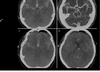

fases q se ven en TC del isquémico

A

hiperaguda

Aguda

Subaguda

Crónica

características fase hiperaguda EVC isquémico

0-6hrs

Hasta 60% sin datos s

ACM hiperdensa

Signo cintura insular

características fase aguda EVC isquémico

7-24hrs

Edema

Borramiento giros y surcos->checa ventriculos y giros

Que signo es el q se ve y de q tipo nos habla

ACM EVC isquemico en fase hiperaguda

Q es y en q fase

evc isquemico en fase aguda x borramiento surcos

Q es

evc isquemico No se ven giros ni surcos